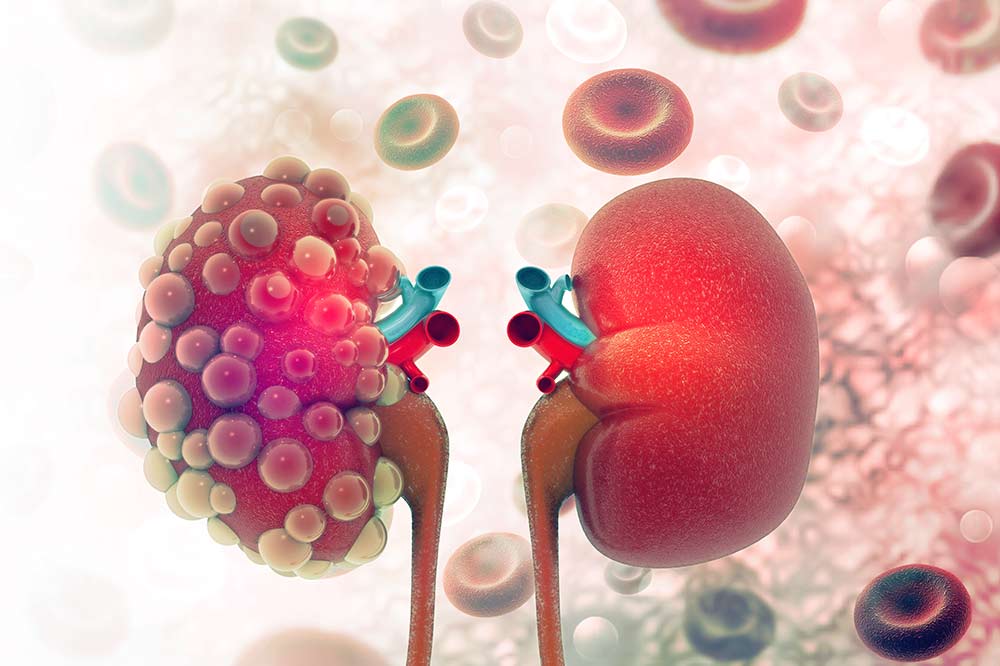

Понимание кавернозного туберкулеза почки